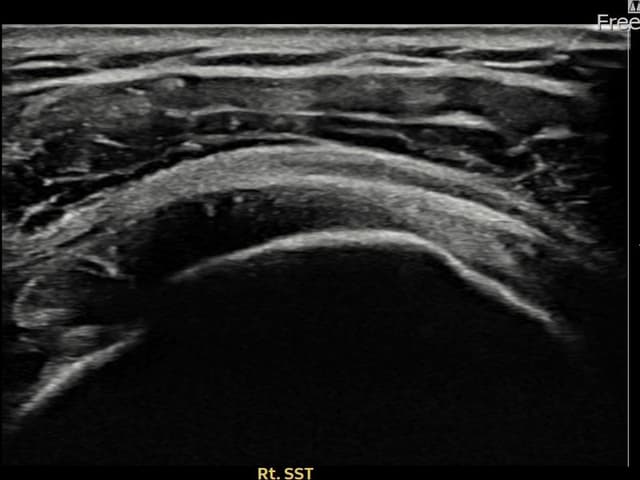

[촬영시기:22.09.05~22.12.08]

[어깨인대 축소봉합술] 우측 어깨 통증과 팔 들어 올리기 제한으로 내원하셨습니다.